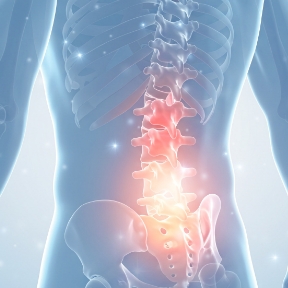

척추압박골절의 주요 증상

아래 증상 중 하나라도 나타난다면

척추압박골절을 의심해 볼 수 있습니다.

허리 주변부에 극심한 통증

누워 있다가 일어날 때 심한 통증

골절 부위 눌렀을 때 압통 발생

심한 통증으로 숨 쉬기가 어려움